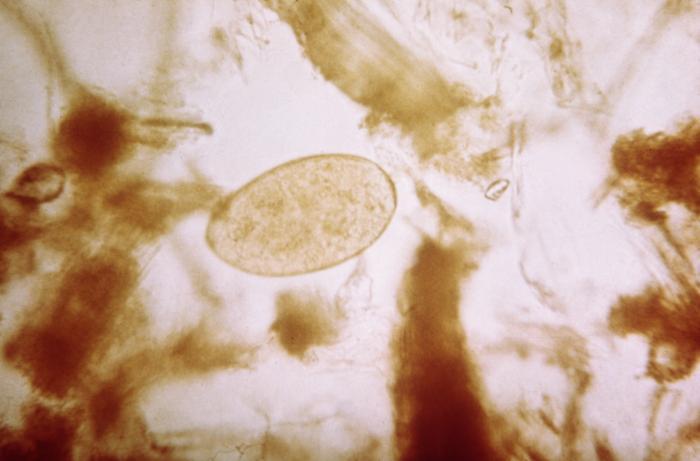

Researchers from Bolivia's FUNDERMA, Institute of Health and Environment, and SEDES La Paz found infections with human fascioliasis, a condition caused by ingesting a parasitic worm that contaminates fresh water and freshwater plants, were practically undetectable following an eight-year MDA campaign with triclabendazole, which is lethal to the worms.

The authors of the study initially had planned to conduct a treatment trial in Bolivia's Altiplano (high plain) region to further explore the effectiveness of triclabendazole against the Fasciola hepatica worms, also known as liver flukes. This region bordering Lake Titicaca is believed to have the world's highest rate of human fascioliasis infections, which start out causing fever and abdominal pain before progressing to a chronic condition that can produce nausea, jaundice, and bacterial infections. But the scientists say they were surprised when they "found it impossible to identify sufficient subjects." In one area, where in 1999 about 27% of the population was infected, in 2017 only 0.7% was infected.